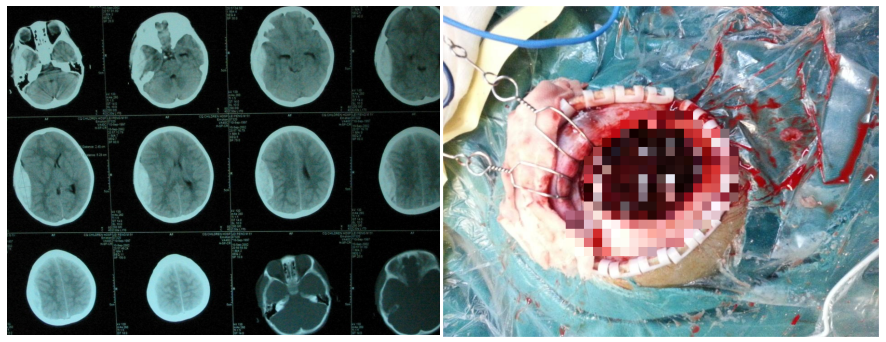

2.颅脑创伤

·小儿外伤性颅骨凹陷粉碎性骨折

·创伤性硬膜外血肿

3.颅内肿瘤